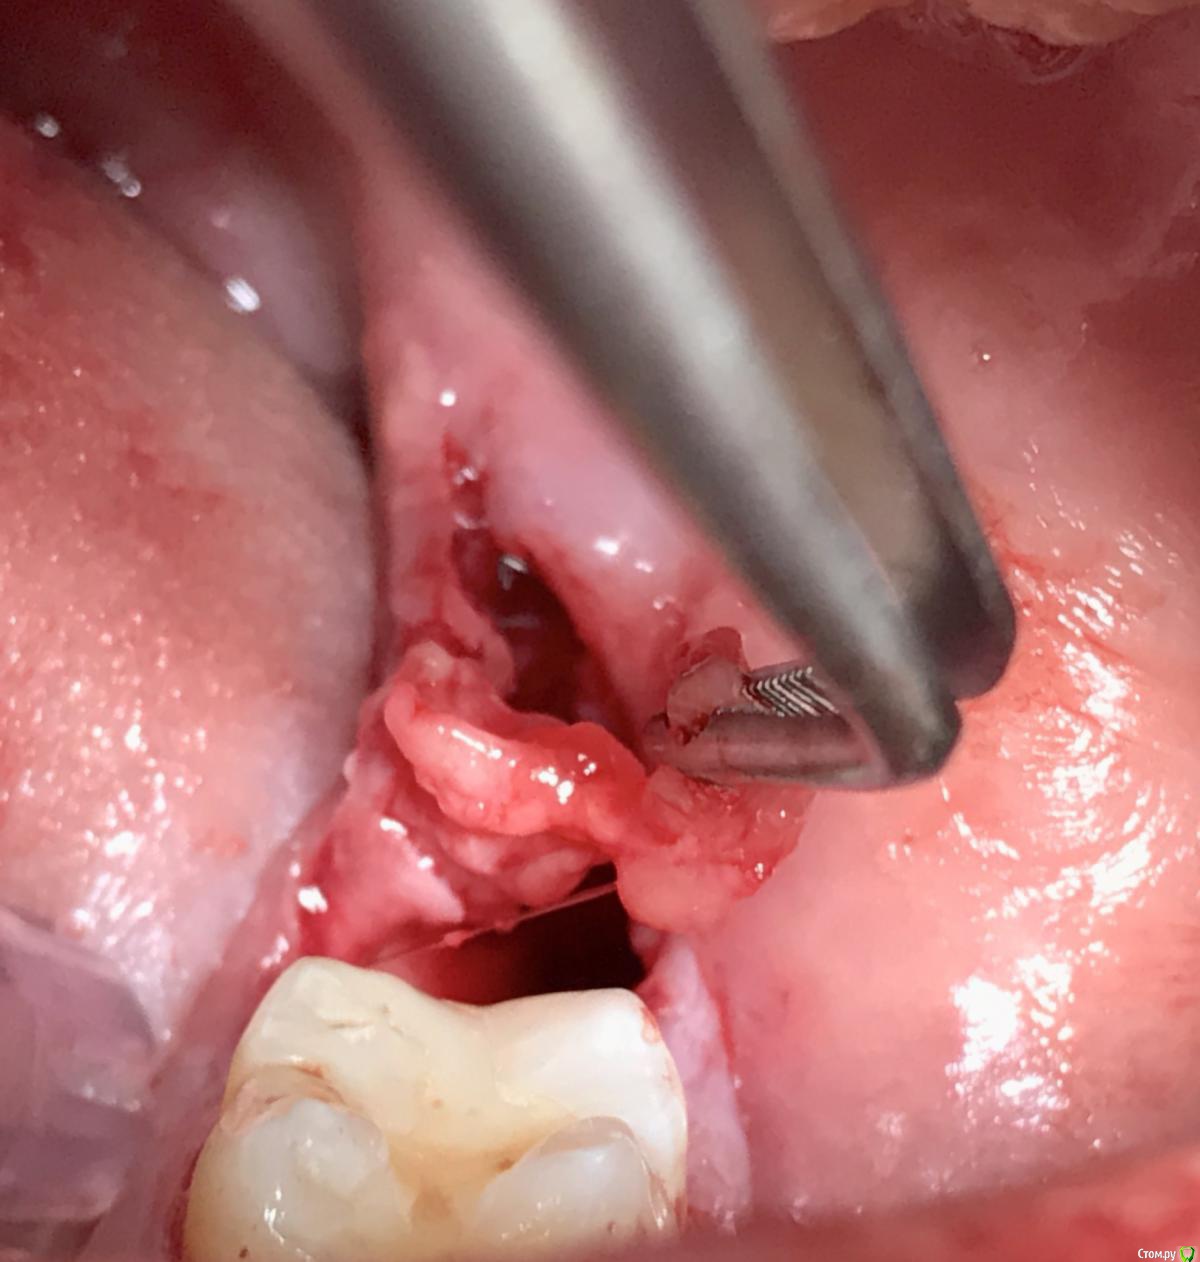

kriokov Опубликовано 4 апреля, 2017 Поделиться Опубликовано 4 апреля, 2017 (изменено) здесь после удаления ретенированного 48 , более менее зажило. Без изысков, доступ сулькулярно, и далее по ретромолярному. Инструмент- тот , что на столе. Шовник - ультрасорб 4\0, моно, но резорбируемый. Поэтому один из матрацных снимать не стал, концы коротко срезал и все. Видно, что где матрацный- сохраняется оверверт тканей. Клиника обычная - болело сутки, глотать больно сутки, ну и рот не очень открывался. 99% ретенированных примерно так и убираю. За качество фоток крайние извинения. столдо экзекуции , все шикарно, доступ - аэродром сразу после- ой , ой, ой , как хорошо точетверо суток-- чего то мне рана не очень, ну не очень как тоВосемь суток , это до снятия швов- ну вроде терпимовосемь суток, это уже свершилось, сняли швы. (один матрасный не снял, рассосется может быть) Изменено 4 апреля, 2017 пользователем kriokov 5 Ссылка на комментарий

колесников Опубликовано 4 апреля, 2017 Автор Поделиться Опубликовано 4 апреля, 2017 Очень даже! Коронка 8го видимо имела язычное положение? Что в лунке? Обычно проходитесь внутрибороздковым разрезом до 6го? Ссылка на комментарий

kriokov Опубликовано 5 апреля, 2017 Поделиться Опубликовано 5 апреля, 2017 8го видимо имела язычное положение? Что в лунке? Обычно проходитесь внутрибороздковым разрезом до 6го? в лунке видимо пусто, или где нибудь на дне сгусток,да , до середины коронки 6-го, примернотам просто глубоко 8-ой, но ортодонты просили убрать Ссылка на комментарий